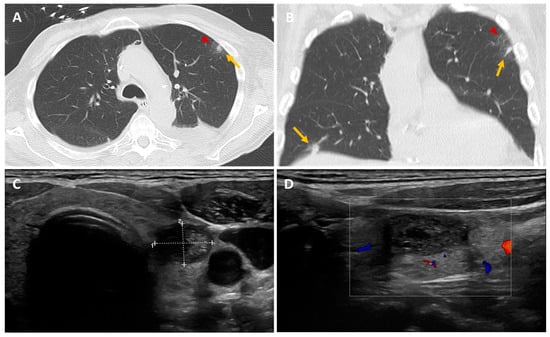

Figure 1. We report the case of a 71-year-old patient admitted to intensive care with severe abdominal-onset sepsis treated with broad-spectrum antibiotics. The patient had undergone liver transplantation for a moderately differentiated hepatocarcinoma operated on more than 1 year previously. During the workup, and given his immunosuppression, an extensive microbiological mapping was carried out (viral, bacterial, parasitic, fungal) which came back positive for Clostridium difficile. Antibiotic therapy was rapidly modulated in the light of our results, with a favorable clinical and biological outcome. In his follow-up, we noted the presence of a positive aspergillary galactomannan antigen, which was checked twice at 7-day intervals. A thoracic CT scan was performed and showed the presence of two pulmonary nodules (yellow arrow) in the left upper lobe with ground glass (red arrow) and the right lower lobe (A,B). A bronchoalveolar lavage (BAL) was achieved and cultured, confirming the presence of Aspergillus Fulmigatus and the diagnosis of pulmonary aspergillosis. An 18F-FDG-PET/CT scan was ordered to assess the presence of any extrapulmonary sites and revealed subcutaneous/muscular nodules and focal hypermetabolism in the left thyroid lobe (Figure 2, yellow arrow). In light of the results, a thyroid workup was carried out; the biological tests came back normal, and the thyroid ultrasound revealed an iso- and hypoechoic EU-TIRADS-5 macro-nodule of the left lobe measuring 18 × 12 × 23 mm, with vascularization around the perimeter, which had been punctured (C,D). Histological results showed the presence of filaments/hyphae scattered throughout in free form or septate and ramified, characteristic of aspergillosis (Figure 3, black arrow). Aspiration and culture revealed the presence of Aspergillus fulmigatus. The diagnosis of invasive thyroid aspergillosis was made. “Dot lines” and number “+” are the ultrasound size measurement tools used to measure the thyroid nodule. The “white square frame” with the colors inside refers to the vascularization of the thyroid nodule. Aspergillosis is a prevalent fungal infection caused by inhaling spores (named conidia) of the mold Aspergillus [1]. These are generally contained in soils, plants, and decaying organic matter, but also in the air and indoor environments. Over 200 species of Aspergillus are currently thought to have been described, of which only around 10% are pathogenic to humans [2]. The genus Aspergillus comprises several hundred species, of which Aspergillus fumigatus remains the most common pathogenic agent, responsible for approximately 90% of cases of aspergillosis, followed by Aspergillus flavus, niger, terreus, and nidulans [3]. In general, aspergillosis is fairly widespread. Depending on the patient’s immunity, they can lead to various forms of clinical presentation, ranging from an isolated form to multi-organ involvement [4]. The most severe forms, known as “invasive”, are usually seen in immunocompromised patients due to HIV infection, oncological conditions, intensive chemotherapy, immunosuppressive drug therapy, post-transplant conditions, or other chronic diseases, and may be associated with high mortality rates and life-threatening illness [5]. It is therefore crucial to assess both the extent of the disease and the effectiveness of treatment, with several diagnostic strategies currently available. The cornerstone of IA diagnosis is biopsy-based fungal culture, supplemented by other biomarker tests such as galactomannan in serum and bronchoalveolar lavage fluid (BAL) [6]. Conventional CT imaging is generally useful in diagnostic management, but radiological features of aspergillosis are not specific, and the CT finding termed the “halo-signal” is a sign that may not always be clearly detectable [7].